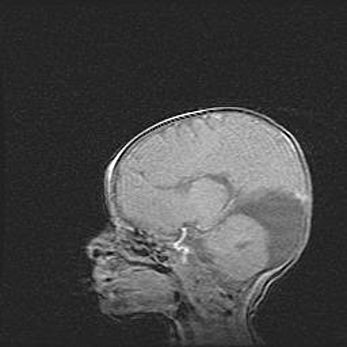

Мальформация Денди-Уокера. Киста задней черепной ямки.

Агенезия мозолистого тела.

Возраст: 2,5 месяца

Вес: 2420 г

Пол: женский

Окружность головы: 37 см

Срок гестации: 32 недели

Мальформация Денди—Уокера — редкий вид патологии ЦНС, представляющий собой врожденный порок развития каудального отдела ствола и червя мозжечка, ведущий к неполному раскрытию срединной (Мажанди) и латеральных (Лушка) апертур IV желудочка мозга. Для этогно синдрома характерна триада симптомов: гипотрофия червя мозжечка и/или полушарий мозжечка, кисты задней черепной ямки, гидроцефалия различной степени. В 70% случаев порок сочетается и с другими аномалиями головного мозга, в частности с агенезией мозолистого тела.